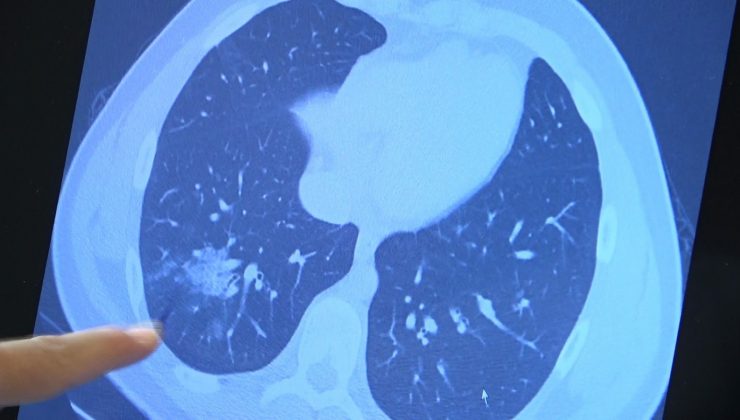

• Aşı olmayan 14 yaşındaki çocukta ciddi akciğer tutulumları görüldü

Aşı olmayan 14 yaşındaki çocukta ciddi akciğer tutulumları görüldü

Korona virüste aşılama yaşı her geçen gün düşerken aşı olmayan çocuklarda da ciddi akciğer tutulumları görülmeye başladı. 12 yaş üzeri kronik rahatsızlığı olan hastalara artık aşılama yapılabiliyor. Göğüs Hastalıkları Uzm. Prof. Dr. Şevket Özkaya ise aşı olmamış kronik rahatsızlığı olan 14 yaşındaki bir çocuğun akciğerlerinde oluşan ciddi tahribatı gözler önüne serdi.

Bazı vatandaşlar hâlâ aşı olmakta tereddüt etmeye devam ederken korona virüs çocuk grubundaki hastaları da etkilemeye başladı. VM Medical Park Samsun Hastanesi Göğüs Hastalıkları Kliniği’nden Prof. Dr. Şevket Özkaya ise aşı olabilecek yaş grubundaki çocukların bir an önce aşılanması gerektiğine vurgu yaptı. 14 yaşında, kronik rahatsızlığı olan ve akciğerlerinde tahribattan dolayı ciddi öksürük, ateş ve nefes darlığı çeken bir hastanın akciğerlerini inceleyen Prof. Dr. Özkaya, “14 yaşındaki kronik rahatsızlığı mevcut olan bir genç hastamızda ciddi akciğer tutulumları var. Her iki akciğerinde de yaygın buzlu cam ve konsolidasyon alanları var. Bu yaştaki çocuklarda beklemediğimiz bir durumdur. Okullarımızda da bu risk var. Okullarımızın açık kalmasının ve sağlık sistemimizin kitlenmemesi için mutlaka aşı olmalıyız. Çocuklarımıza rol model olmalıyız. Şu anda hastanelerimiz hastalara yetişebiliyor. Yatak sayımız yeterli. Ancak kontrollü sosyal hayatımızı düzene sokmadıkça ve aşı olmadıkça, gelecekte hastanelerde yatak sayısı sıkıntısı çekebiliriz” dedi.

“Çocuklarımıza kötü örnek olmamalıyız”

Okulların açılmasıyla ailelerin çocuklarını nasıl salgından koruyacakları konusunda tereddütlerinin başlayacağını ifade eden Prof. Dr. Özkaya, “Aşıda yaş grupları düştükçe, hastalık aşı olmayan yaş gruplarında görülmeye başladı. Artık 15-18 yaşlarında aşılarını olmamış hastalarımız da ciddi akciğer tutulumları ile hastaneye gelebiliyorlar. Çocuklarımıza maalesef kötü örnek olduk. Maske, mesafe ve kontrollü sosyal hayatımızı tam doğru olarak gerçekleştiremedik. Bunları okullarda çocuklardan istememiz çok zor olacak. Çocuklarımızı korumanın birinci yolu aşıdır. Mutlaka aşı yaşı gelmiş her öğrencimizin aşı olması gerekiyor. Aşı çağı gelmemiş çocuklarımızın ise özellikle ailesinde anne, baba ve daha büyük ebeveynlerinin, anneannelerin, dedelerin aşılanması gerekiyor. Çocuklara rol model olmamız gerekiyor. Maske, mesafe, temizlik felsefesini çocuklara örnek olarak göstermeliyiz. Okulların açık kalması iki koşula bağlıdır. Birincisi aşı yaşına gelmiş çocuklarımızın aşılanmalarıdır. İkincisi aşı yaşına gelmemiş çocukların büyüklerinin aşılanmalarıdır” diye konuştu.